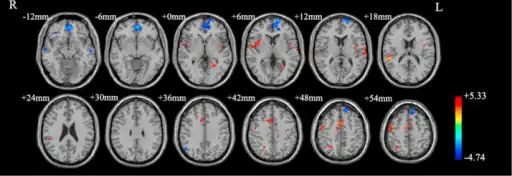

Functional neuroimaging during symptom provocation has observed abnormal activity in the orbitofrontal cortex, left dorsolateral prefrontal cortex, right premotor cortex, left superior temporal gyrus, globus pallidus externus, hippocampus and right uncus. Weaker foci of abnormal activity were found in the left caudate, posterior cingulate cortex and superior parietal lobule.[61] However, an older meta analysis of functional neuroimaging in OCD reported the only consistent functional neuroimaging findings have been increased activity in the orbital gyrus and head of the caudate nucleus, while ACC activation abnormalities were too inconsistent.[62] A meta analysis comparing affective and non affective tasks observed differences with controls in regions implicated in salience, habit, goal-directed behavior, self-referential thinking and cognitive control. For non affective tasks, hyperactivity was observed in the insula, ACC, and head of the caudate/putamen, while hypoactivity was observed in the medial prefrontal cortex (mPFC) and posterior caudate. Affective tasks were observed to relate to increased activation in the precuneus and posterior cingulate cortex(PCC), while decreased activation was found in the pallidum, ventral anterior thalamus and posterior caudate.[63] The involvement of the cortico-striato-thalamo-cortical loop in OCD as well as the high rates of comorbidity between OCD and ADHD have led some to draw a link in their mechanism. Observed similarities include dysfunction of the anterior cingulate cortex, and prefrontal cortex, as well as shared deficits in executive functions.[64] The involvement of the orbitofrontal cortex and dorsolateral prefrontal cortex in OCD is shared with bipolar disorder and may explain their high degree of comorbidity.[65] Decreased volumes of the dorsolateral prefrontal cortex related to executive function has also been observed in OCD.[66]

People with OCD evince increased grey matter volumes in bilateral lenticular nuclei, extending to the caudate nuclei, with decreased grey matter volumes in bilateral dorsal medial frontal/anterior cingulate gyri.[67][68] These findings contrast with those in people with other anxiety disorders, who evince decreased (rather than increased) grey matter volumes in bilateral lenticular / caudate nuclei, as well as decreased grey matter volumes in bilateral dorsal medial frontal/anterior cingulate gyri.[68] Increased white matter volume and decreased fractional anisotropy in anterior midline tracts has been observed in OCD, possibly indicating increased fiber crossings.[69]